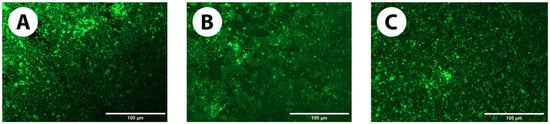

3.2.3. Live/Dead Assay